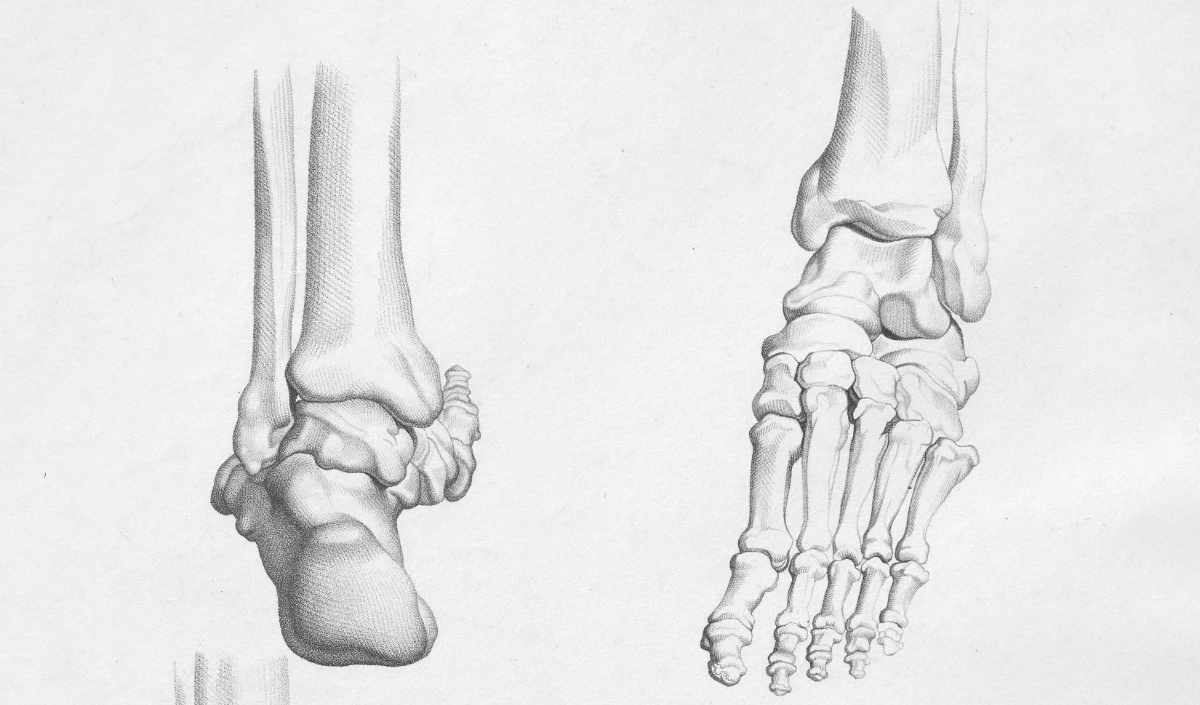

3 मिनट में हड्डी जोड़ने वाला ‘बोन ग्लू’: चीन का नया चमत्कार? China Develops Fast Bone Glue

उन्होंने एक ऐसा बोन ग्लू विकसित किया है जो मात्र तीन मिनट में टूटी हुई हड्डियों को जोड़ सकता है।

यह बोन ग्लू रक्त से भरपूर वातावरण में भी प्रभावी ढंग से काम करता है, हड्डियों के टुकड़ों को दो से तीन मिनट में जोड़ देता है।

यह नई तकनीक फ्रैक्चर के उपचार में एक महत्वपूर्ण बदलाव ला सकती है, रोगियों के लिए उपचार का समय कम कर सकती है और बेहतर स्वास्थ्य परिणाम प्रदान कर सकती है।

यह तकनीक हड्डी के प्रत्यारोपण और अन्य हड्डी संबंधी सर्जरी को भी सरल और कुशल बना सकती है।